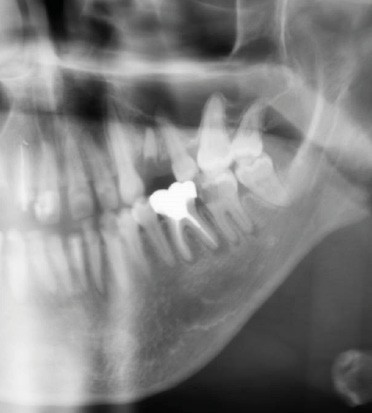

Le principal risque d’ostéonécrose en lien avec une biothérapie est dû à l’inhibiteur du RANKL, le dénosumab (commercialisé sous le nom de Xgeva® en indication oncologique, Prolia® en indication rhumatologique) (fig. 1). Cet anticorps bloque la liaison du RANKL à son récepteur, qui permet notamment l’activation des ostéoclastes. La résorption osseuse est alors bloquée, action intéressante dans le cadre d’une ostéoporose ou de métastases osseuses. Cependant, même si le mécanisme d’action est totalement différent, on retrouve les mêmes effets indésirables que ceux observés avec les bisphosphonates au niveau de la cavité orale. Les patients traités par anti-RANKL présenteront un risque d’ostéonécrose des mâchoires. Ce risque sera évidemment plus ou moins important en fonction de facteurs à rechercher : indication du traitement (oncologique ou rhumatologique), durée totale du traitement, date de dernière administration, corticothérapie associée, diabète, présence de foyers infectieux bucco-dentaires…

D’autres biothérapies sont susceptibles d’entraîner ce même type de risque infectieux local à type d’ostéonécrose, comme les anti-angiogéniques. Cependant, leur rôle est discuté dans la littérature ; ils semblent agir davantage comme facteur de risque lorsqu’ils sont associés aux bisphosphonates ou au dénosumab, que comme une cause isolée.